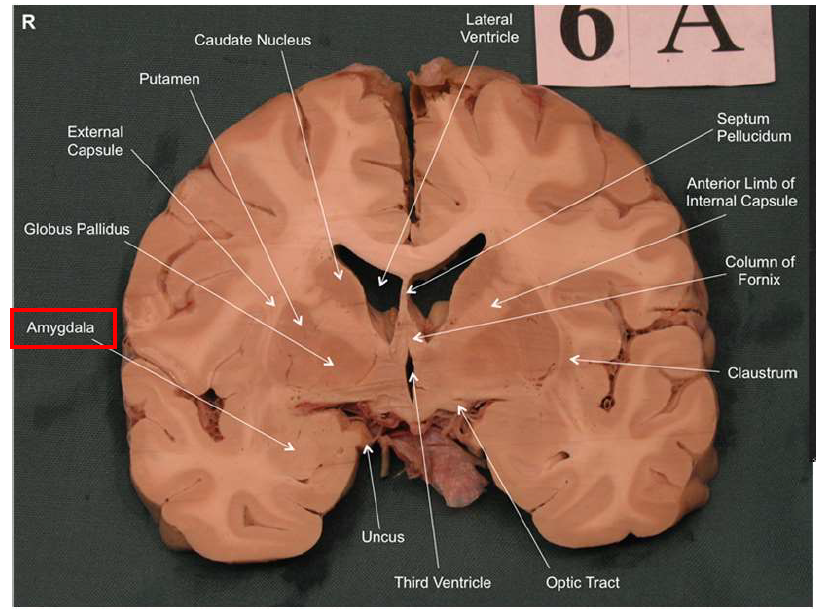

What is the function of the amygdala?

Emotions & Memory Hub

Processes emotions (esp. fear & pleasure)

Helps us remember emotional experiences

Imagine the amygdala as a fire alarm in your brain. When it senses danger (fire!), it triggers the alarm (fight-or-flight response) almost instantaneously and remembers the event vividly (emotional memory)